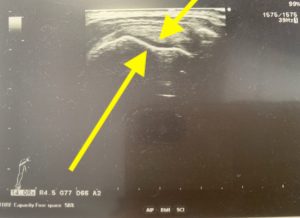

先生はエコーで肩の筋肉を見ながら、どこに生理食塩水を入れたらいいかを見てくれます。食塩水を入れることで、固まってくっついている筋膜をはがすのです。

生理用食塩水を入れるとこのように白くなっている部分が黒く変わりました。

(筋肉がくっついてしまっているところは、白い層がたくさんくっついてしまっています。)

このようなエコーを一緒に見ながら、先生が注射をするので安心できました。